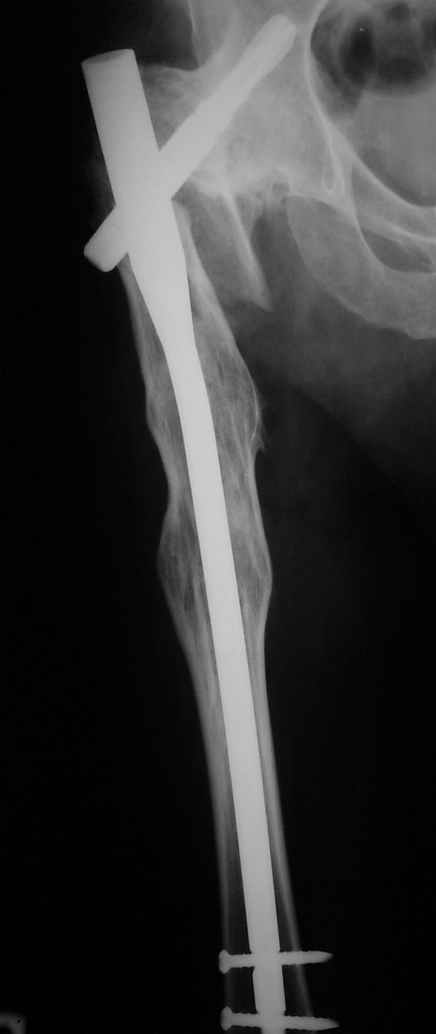

Рентгенограммы до и после. Больной профессор на кафедре сопромата и после детального изучения

особенностей имплантата, собственных рентгенограмм дал добро на операцию. Ваш вариант лечения вполне симпатичен.